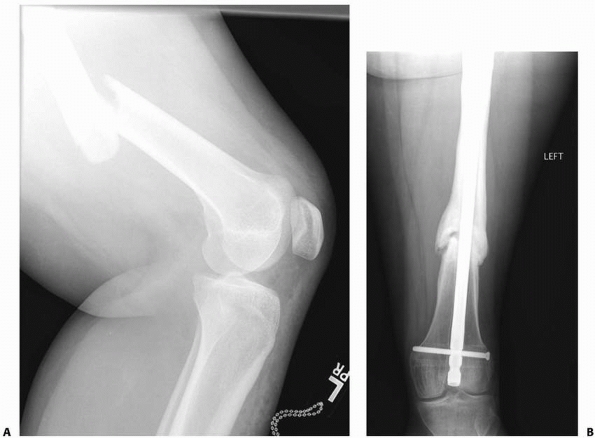

![]() |

FIGURE 22-11

Tibial epiphyseal injury in association with tibial pin traction treatment for a femoral fracture. A 14-year-old boy sustained a femoral fracture that was treated by tibial skeletal traction. Two years later, the fracture was well healed but 2.5 cm short. A recurvatum deformity of the same side was apparent. A. An apparent fusion of the tibial tubercle. B. The bridge was confirmed by tomography. C. Bridge resection was performed with free fat interposition. A marker was placed to facilitate subsequent evaluation of growth. A tibial pin, if used, should be inserted posterior to the anterior aspect of the tibial tubercle. |